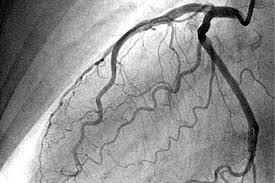

De acuerdo con las guías del Colegio Americano de Cardiología y la Asociación Americana del Corazón (ACC/AHA), los pacientes que presentan características de alto riesgo (como se detalla en la Tabla 10-7) generalmente deben someterse a una estrategia invasiva temprana que incluye la cateterización y la revascularización. Estas características de alto riesgo pueden incluir factores como elevaciones significativas en los biomarcadores cardíacos, cambios en el electrocardiograma o la presencia de síntomas persistentes a pesar del tratamiento inicial.

El ensayo ICTUS ha proporcionado evidencia adicional sobre el manejo de estos pacientes, mostrando que una estrategia basada en la angiografía coronaria selectiva y la revascularización, en función de la inestabilidad clínica o la isquemia inducible (incluso en pacientes con troponina positiva), es una opción aceptable. Esta estrategia, recomendada como clase IIb por las guías ACC/AHA, sugiere que, para algunos pacientes con elevaciones de troponina, puede ser adecuado realizar una evaluación más específica antes de proceder a una intervención invasiva, en lugar de adoptar una estrategia invasiva universal.